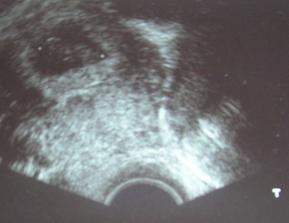

18.září jsme byli na našem 1.IVF... a 8.den od ET se mi "zjevily" nádherné // 🙂... přeju si,aby se všechno vyvíjelo dobře... 29.9 11.den po ET mi pro zhoršení OHSS provedli punkci Douglasova prostoru a odsáli 2 litry žlutého ascitu ☹ Nicméně se mi ulevilo 🙂 HCG ten den 259... 6.10 kontrola HCG - 2950 (18.den od ET)... 10.10 UTZ - čekáme DVOJČÁTKA 🙂 🙂 🙂... 17.10 krvácení a následná hospitalizace, UTZ - dvojčátkům bijí srdíčka, 20.10 HCG - 56000, 25.10 propuštění z nemocnice... 31.10 poslední kontrola v CARu, dvojčátka mají 2 a 2,1 cm... 11.11 UTZ - dvojčátka mají 3 cm... 24.11 UTZ - dvojčátka mají 9 cm (ale moc se mi to měření nezdá, ve čtvrtek na screeningu se ukáže pravda, čeká nás 3D 🙂) 27.11 screening I.trimestru - miminka jsou zdravá, od hlavičky po prdelku mají 7 cm... 19.12 3D - miminko "A" je chlapeček, "béčko" chce zůstat zatím v utajení 🙂 tak snad příště 🙂... 8.1 3D - miminko "B" je holčička 🙂 19.1 echokardiografie - obě srdíčka jsou zdravá 🙂 20.1 screening II.trimestru - vše OK, miminka mají 360 a 364 gramů 🙂 26.1 UTZ - chlapečkovi se ztratil pindík a najednou čekáme 2 holčičky 🙂) Doufám, že už je to definitivní 🙂) 19.2 UTZ 3D4 - holčičky potvrzeny!!! 🙂 mají každá téměř 800 gramů! 🙂 20.3 UTZ - holčičky mají 1700 a 1800 gramů! 8.4 UTZ - holky mají neuvěřitelné váhy 2415 a 2600 gramů! 11.5 nástup do nemocnice... 11.května ve 20,03 se nám akutním císařským řezem narodila Eliška (2970/48) a o minutu později Nelinka (3200/50).Jsme nejšťastnější rodiče na světě! 🙂